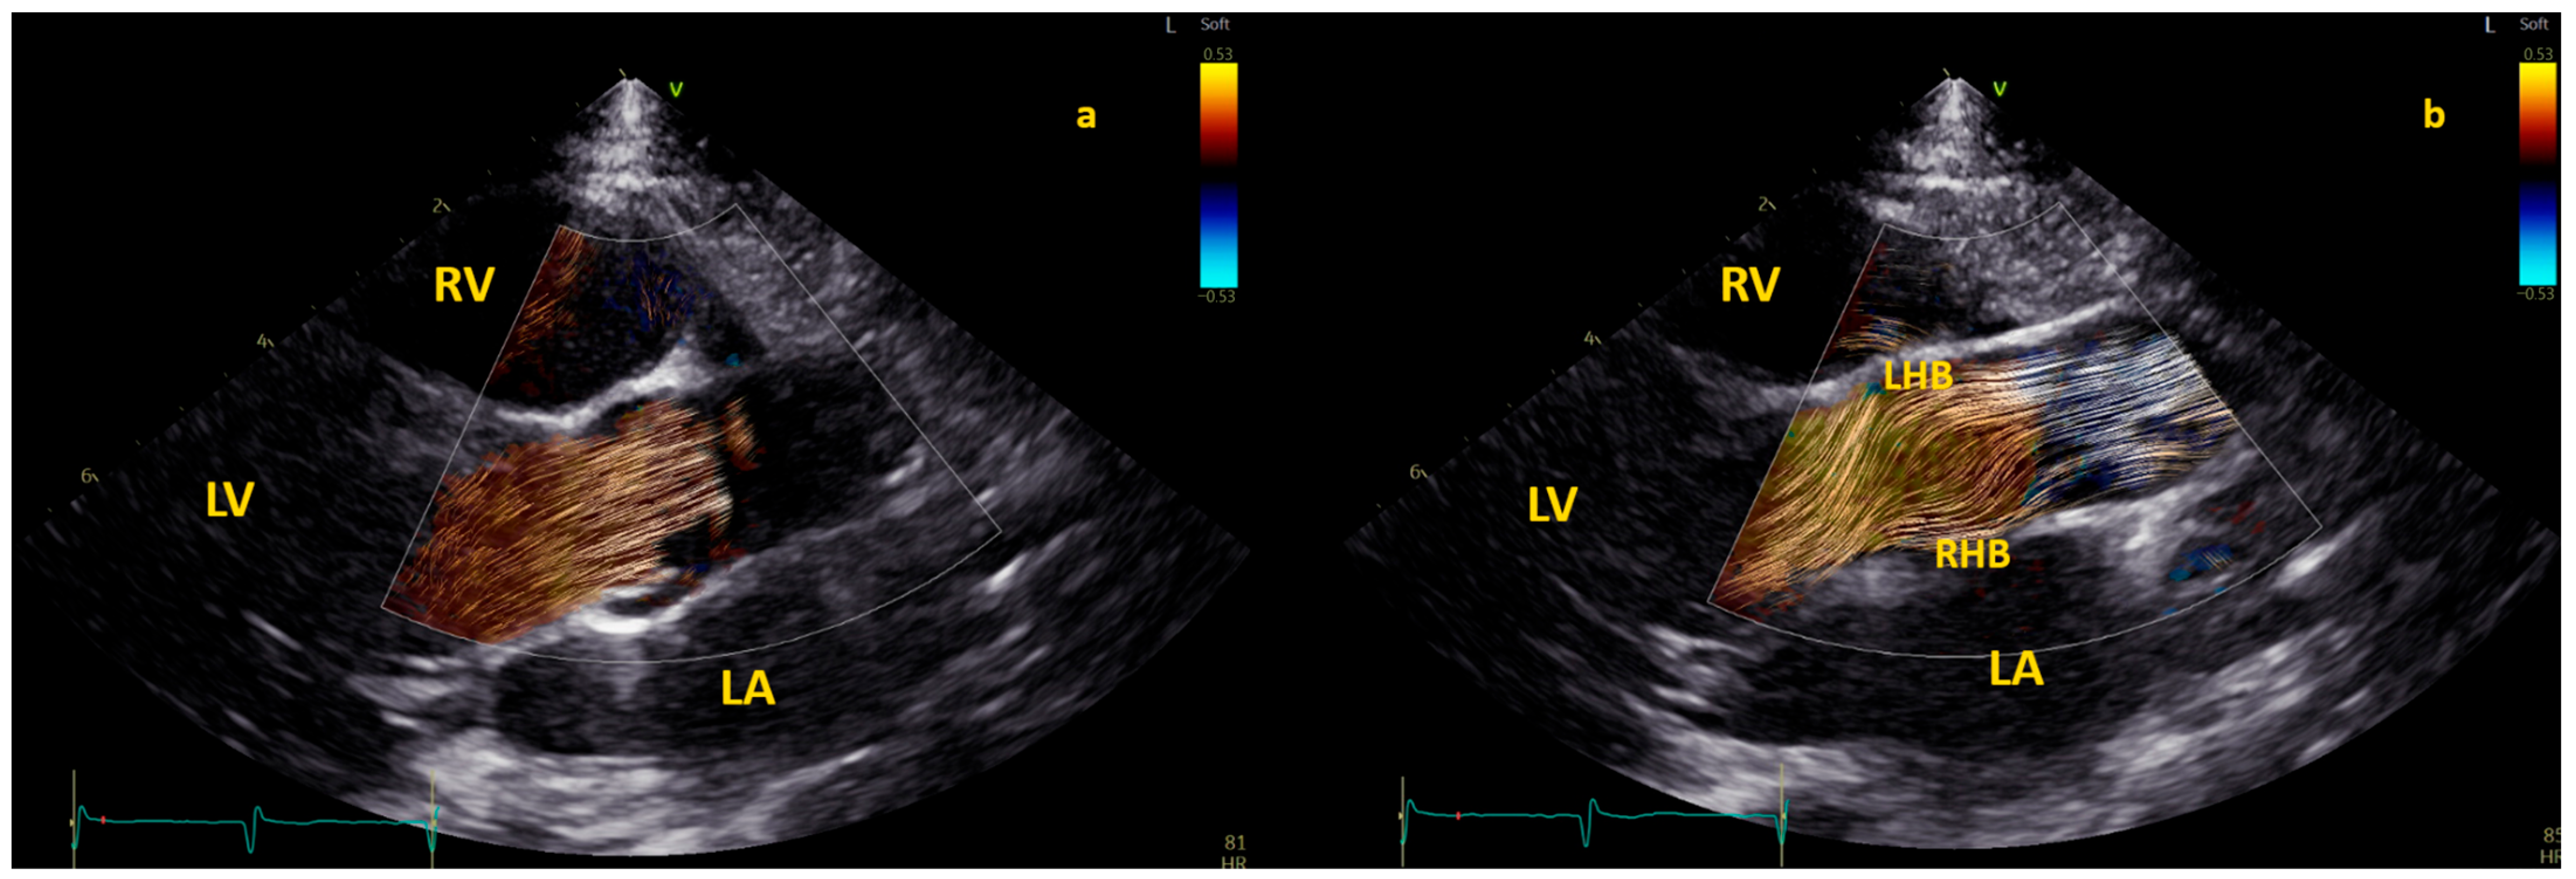

Examples of physiological and pathological left ventricular vortices are provided in Figure 2).

Figure 2. Comparison of left ventricle (LV) diastolic vortex in a healthy heart (a) and in a heart with left ventricular volume overload due to a significant patent arterial duct (b). BST images were acquired by zoom on an apical 4-chamber view, including both the interventricular septum and the mitral valve. Position of the vortex was calculated in relation to two lines: (1) a line from the ventricular apex to the mitral valve, and (2) a line from the IVS to the LV free wall. Vortex height was determined by measuring the longitudinal dimension of the main vortex relative to LV length, and vortex width as the horizontal dimension of the vortex relative to LV width. The vortex in (b) has a different size and position (further from the interventricular septum and with a larger area) compared to the healthy counterpart. LA = left atrium; LV = left ventricle; RA = right atrium; RV = right ventricle.